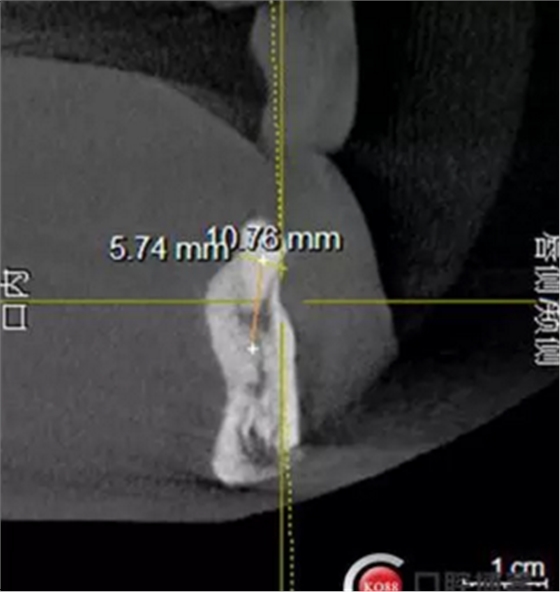

檢查:上頜無牙頜假牙穩(wěn)定性尚可,下頜3435364243殘根;33殘冠1-2度松動,其他牙齒缺失;CBCT檢查:下頜牙槽骨前牙區(qū)骨高度足,后牙區(qū)骨高度最低為8mm,骨寬度足。

1)術前檢查,拍攝臨床照片及CBCT檢查,制取活動義齒參考模型,指導后期最終修復的牙齒排列

2)術前準備及手術過程,測量血壓及血糖,簽種植知情同意書;嚴格遵循無菌操作,局麻下采用微創(chuàng)技術于323436分別植入osstem4.0X10,4.0X10,4.5X7; 434446分別植入osstem4.0X1O,4.0X10,4.5X7.初期穩(wěn)定性均達到了35N.CM以上;嚴密縫合,止血,種植體位點和方向與設計一致。